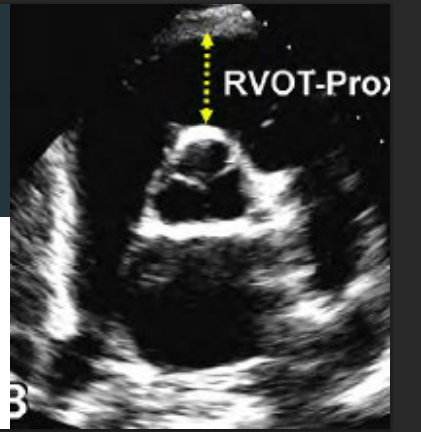

How do measure the RV in PLAX and whats the abnormal number?

Diameter measured at end diastole.

Inner edge of RV to the septal aortic junction.

Abnormal is >3.0 cm

How do you measure the RV diameter in PSAX at the great vessel view prox?

Whats the abnormal number?

Inner edge of RV to the aortic root

Abnormal is >3.5 cm